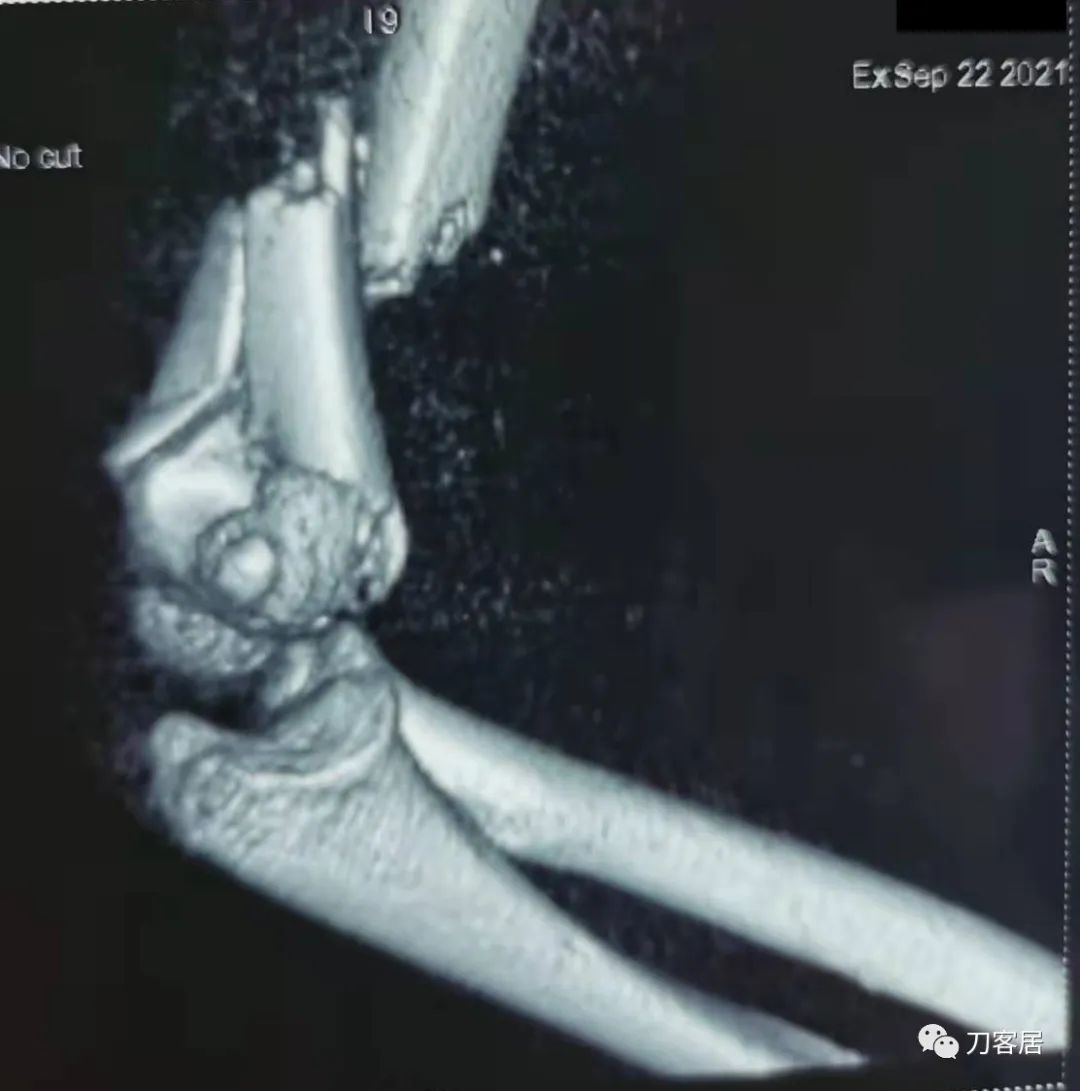

20210922当地省中医院三维CT01

20210922当地省中医院三维CT02

20210922当地省中医院三维CT03

20210922当地省中医院三维CT04

查体:左侧肘关节肿胀明显、疼痛、畸形,局部可见明显青紫瘀斑,左肘关节活动受限,肱骨远端环形压痛(+),局部可及异常活动及骨擦感形成,左上肢末梢桡动脉可触及,左侧腕关节及拇指背伸活动受限,左侧虎口区感觉麻木。辅助检查:自带X线及CT片示:左肱骨髁间粉碎性骨折。

入院诊断:1. 左肱骨髁间粉碎性骨折;2.左肱骨远端骨骺损伤;3. 左桡神经损伤。